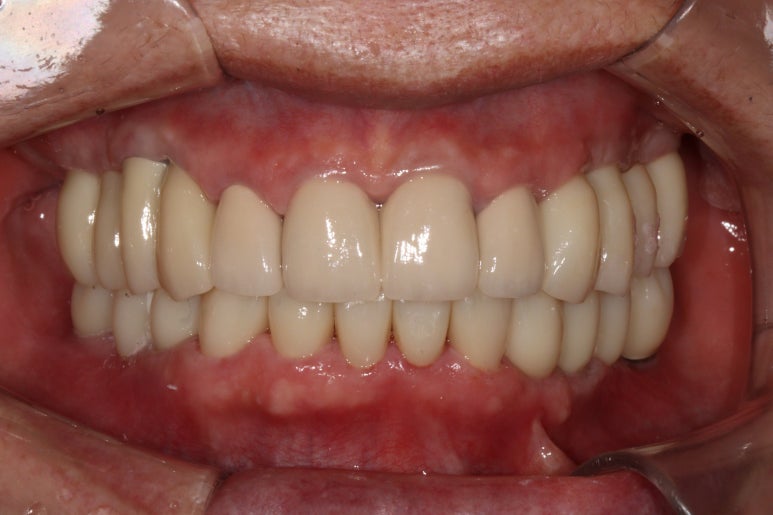

그렇게 완성된 최종 보철물 형태입니다.

임시치아와 다르게 지르코니아 크라운으로 제작되어 훨씬 단단하고 매끈하고 이상적인 형태를 가진걸 보실 수 있으실거에요.

위 아래 앞니 모두 적절한 길이로 회복이 되었고, 어금니도 이상적인 형태를 보여주고 있습니다.

제거가 덜 된 접착제가 조금 보이긴 하지만,

좌우로 옆에서 봤을 때도 충분히 기능이 잘 되게끔 잘 물리는 어금니를 보실 수 있을거에요.

식사 시 음식이 덜 끼도록 치아와 치아사이를 최대한 닫아놓은 모양입니다.

위아래 모두 아주 이상적인 형태로 제작된 치아모양의 지르코니아 크라운을 보실 수 있을거에요.

이 정도면 전체 구강 재건 (full arch rehabilitation)이라고 불러야 합니다.

솔직히 제가 봐도 미라클한 최종 치료 사진...

이렇게 잘해도 되는건가요..!!!

적절한 색조와 형태를 가진 앞니 보철물.. 그리고 적절히 기능하도록 설정된 아래턱의 위치

모든것이 조화롭게 완성된 치료 후 구강내 사진입니다.

환자분도 정말 너무너무 대만족 하셨어요 :)